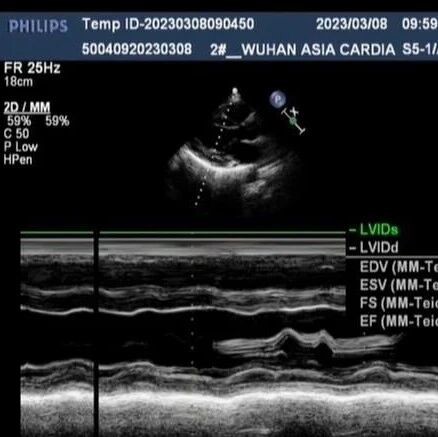

“双梗并发,嗜酸为祸”——特发性嗜酸粒细胞增多症并发心肌梗死与脑梗死一例